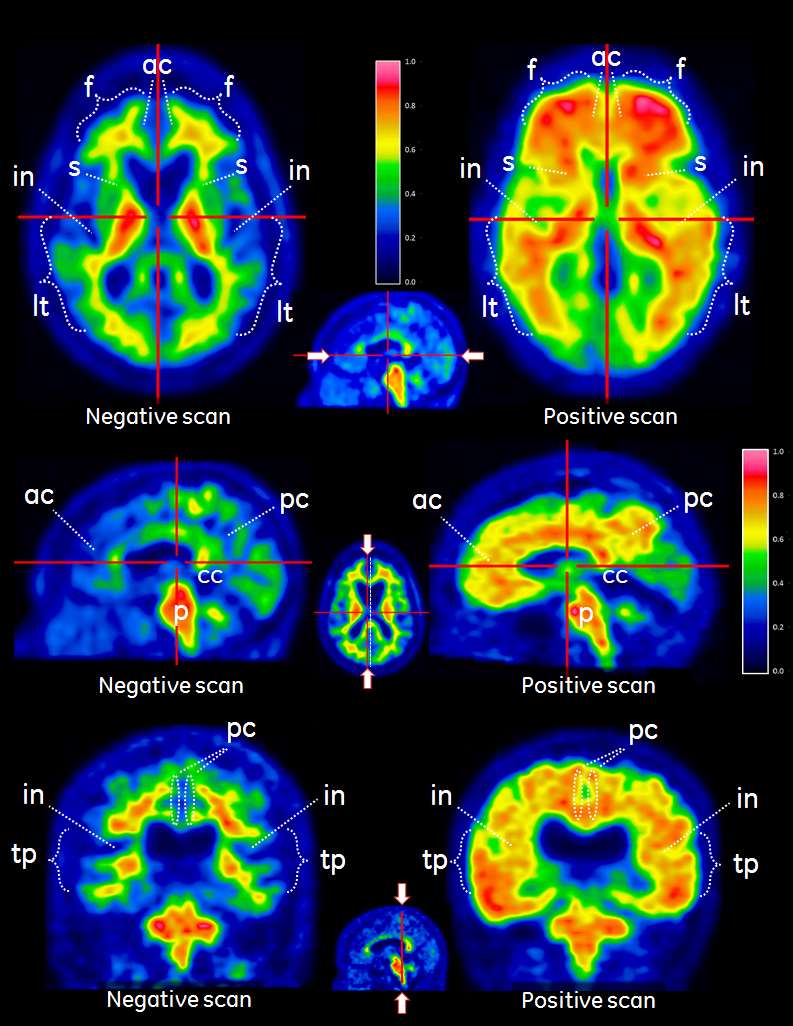

PET-Bilder sollten mithilfe einer Sokoloff-, Regenbogen- oder Spektrum-Farbskala ausgewertet werden. Der Auswerter sollte die Signalstärke in der kortikalen grauen Substanz mit der maximalen Signalstärke in der weissen Substanz vergleichen. Die Bilder sollten systematisch ausgewertet werden (siehe Abbildung 1). Beginnend auf Ebene des Pons (p) wird nach oben gescrollt über

·Die Frontallappen und anteriores Cingulum (f, ac, axiale Ansicht)

·Posteriores Cingulum und Precuneus (pc, sagittale Ansicht)

·Temporo-parietale Aspekte einschliesslich Insula (in, axiale Ansicht und tp-in, koronare Ansicht)

·Laterale Temporallappen (It, axiale Ansicht)

·Striatalregion (s, axiale Ansicht)

Die Interpretation der Bilder erfolgt visuell durch Vergleich der Aktivität in der kortikalen grauen Substanz mit der Aktivität der angrenzenden kortikalen weissen Substanz.

·Das Muster einer Region wird als negativ (normal) angesehen, wenn das Tracersignal in den kortikalen Regionen niedrig ist (d. h. deutlich niedrigere Signalintensität im Vergleich zur angrenzenden weissen Substanz und ähnliche Intensität wie in den Regionen des Kleinhirns, die viel graue Substanz aufweisen). Auf den Bildern ist das Signal in Regionen grauer Substanz nicht vollständig abwesend, da Tracerbindung in angrenzenden Regionen weisser Substanz aufgrund von PET-Partialvolumen-Auflösungseffekten die Regionen grauer Substanz beeinflusst.

·Eine Region wird als positiv (abnormal) angesehen, wenn das Tracersignal in den Kortikalregionen hoch erscheint (d.h. etwa gleiche oder höhere Signalintensität als die angrenzende weisse Substanz und höhere Signalintensität als die Regionen des Kleinhirns, die viel graue Substanz aufweisen).

·Wenn einer dieser Bereiche deutlich positiv (abnormal) ist, sollte das Bild als positiv (abnormal) klassifiziert werden. Anderenfalls sollte es als negativ (normal) klassifiziert werden.

Abbildung 1

VIZAMYL-PET-Fälle mit Beispielen eines negativen Flutemetamol (18F) PET-Scans (links) und eines positiven Scans (rechts). Gezeigt werden die axiale Darstellung (erste Reihe), sagittale Darstellung (zweite Reihe) und koronare Darstellung (dritte Reihe).

Abbildung 1. Axiale (a), sagittale und koronare Sicht eines negativen (links) und positiven (rechts) Flutemetamol (18F) Scans. Die negativen Scans zeigen ein sulkales/gyrales Muster der weissen Substanz. Die sulkalen und gyralen Muster sind in den positiven Scans rechts nicht erkennbar. Zu beachten ist, dass auf den positiven Scans die Intensität in den Bereichen der grauen Substanz höher ist (>60 % des Maximums) im Vergleich zu den negativen Scans, und dass die Intensität in einer scharfen konvexen Kante zum Rand strahlt. Die negativen Scans zeigen eine spitz zulaufende Intensität zu den Randbereichen des Gewebes hin. Zu beachten sind auch die medialen Bereiche, in denen höhere Intensitäten in der grauen Substanz auf den positiven Bildern rechts zu sehen sind.

Legende: Graue Substanz – f frontales und ac anteriores Cingulum, pc posteriores Cingulum und Precuneus, lt lateral temporal, tp temporo-parietal und in Insula, s Striatum. Weisse Substanz – p Pons und cc Corpus callosum.